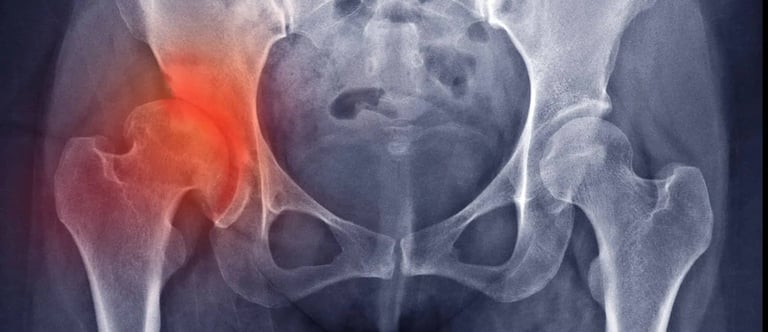

La dysplasie de la hanche est une affection fréquente qui affecte l'articulation de la hanche chez les chiens. Cette affection se manifeste par une déformation de l'articulation de la hanche, provoquant une instabilité et, à terme, de l'arthrose (parfois dès l'âge de 10 à 12 mois). Elle est liée à une hyperlaxité de la tête fémorale dans sa cavité acétabulaire. Souvent bilatérale, les hanches peuvent toutefois être touchées de manière asymétrique.

Diagnostic :

Il existe plusieurs examens possibles à effectuer auprès de votre vétérinaire :

- Test d’Ortolani : Si laxité il y a, on observe une subluxation.

- Dépistage radio à 12 mois (méthode OFA) : on mesure l’angle de Norberg-Olsson qui quantifie la laxité articulaire.

- Calcul de l’indice de distraction (méthode PennHIP) : on mesure l’angle entre la tête fémorale et l’acétabulum, ce qui classifie la gravité de la dysplasie.